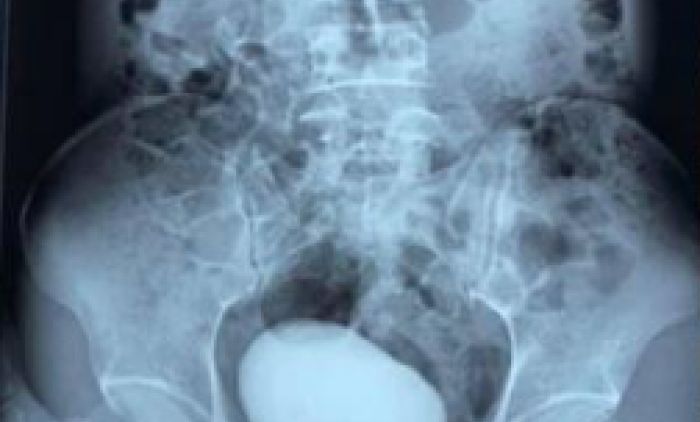

Jedna snimak sa skenera iz vijetnamske bolnice zapanjio je čitav svet.

Jedna Vijetnamka došla je u Hitnu žaleći se na jak bol u predelu stomaka, ali i ispod njega.

Kako nije mogla više da trpi bolove, medicinski radnici su je poslali na skener koji je pokazao ogromnu, okruglu masu u mokraćnom kanalu. To je bio kamen dug deset centimetara i težak 400 grama!

Fotografije kamena od 400 grama obišle su društvene mreže u Aziji, a mnogi se pitaju kako je uopšte žena mogla da podnosi takvu bol.